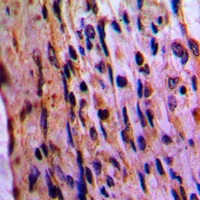

Immunohistochemical analysis of EIF3D staining in human lung cancer formalin fixed paraffin embedded tissue section. The section was pre-treated using heat mediated antigen retrieval with sodium citrate buffer (pH 6.0). The section was then incubated with the antibody at room temperature and detected using an HRP conjugated compact polymer system. DAB was used as the chromogen. The section was then counterstained with haematoxylin and mounted with DPX.